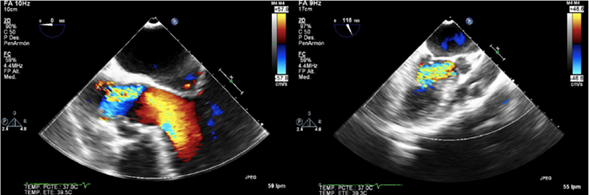

Figura 1 Imagen tomada durante ecocardiografía transesofágica en la cual se evidencia turbulencia del flujo en la válvula aórtica y el tracto de salida del ventrículo izquierdo, explicada por insuficiencia aórtica severa.

Paciente masculino de 56 años, con antecedente de hipertensión arterial, quien consultó a una institución de tercer nivel de Medellín por cuadro clínico de tres días de evolución consistente en parestesias y hemiparesia del hemicuerpo derecho, asociado a disartria y asimetría facial; negaba síntomas cardiovasculares. Una tomografía de cráneo simple realizada a su ingreso, mostró área hipodensa en región gangliobasal izquierda compatible con lesión isquémica. Se amplió estudio para determinar etiología del infarto cerebral, encontrando VDRL reactivo en 128 dils y FTA-ABS positivo. En ecocardiografía transesofágica se evidenció válvula aórtica trivalva con insuficiencia severa, secundaria a perforación de la valva coronariana derecha, dilatación de la raíz aórtica con engrosamiento intimal difuso y calcificaciones en la unión sinotubular y en la curvatura menor del cayado aórtico (fig. 1). Se practicó arteriografía coronaria en la que se encontró dilatación de la aorta torácica ascendente con formación de aneurisma en el tercio medio del cayado aórtico y oclusión en el ostium de la arteria coronaria derecha. Una angiotomografía de tórax confirmó dilatación aneurismática de la aorta ascendente de 45 mm de diámetro (fig. 2). En vista de los hallazgos imagenológicos descritos en presencia de serología reactiva para sífilis, se consideró probable aortitis sifilítica. Se hizo recambio valvular aórtico exitoso, por bioprótesis y bypass aorto-coronario a la descendente posterior (fig. 3). El aneurisma de la aorta ascendente no cumplía criterios de diámetro que obligaran a su corrección. El estudio histológico del material quirúrgico arrojó cambios degenerativos; en la aorta se observó vasa vasorum con infiltrado inflamatorio de células mononucleadas, mientras que la tinción de Warthin-Starry fue negativa.